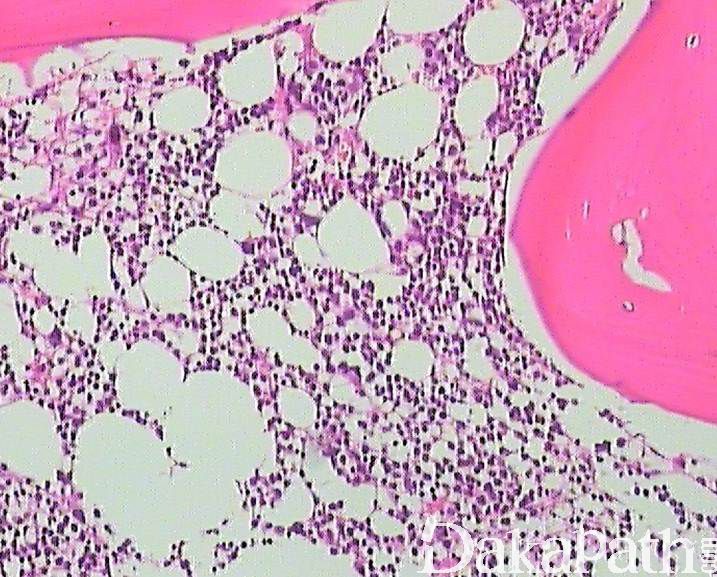

- 骨髓活检:细胞密度通常增高 或正常(少数减低),巨核细胞异型性常更明显,原始细胞可以正常或不同程度增高(<20%)。